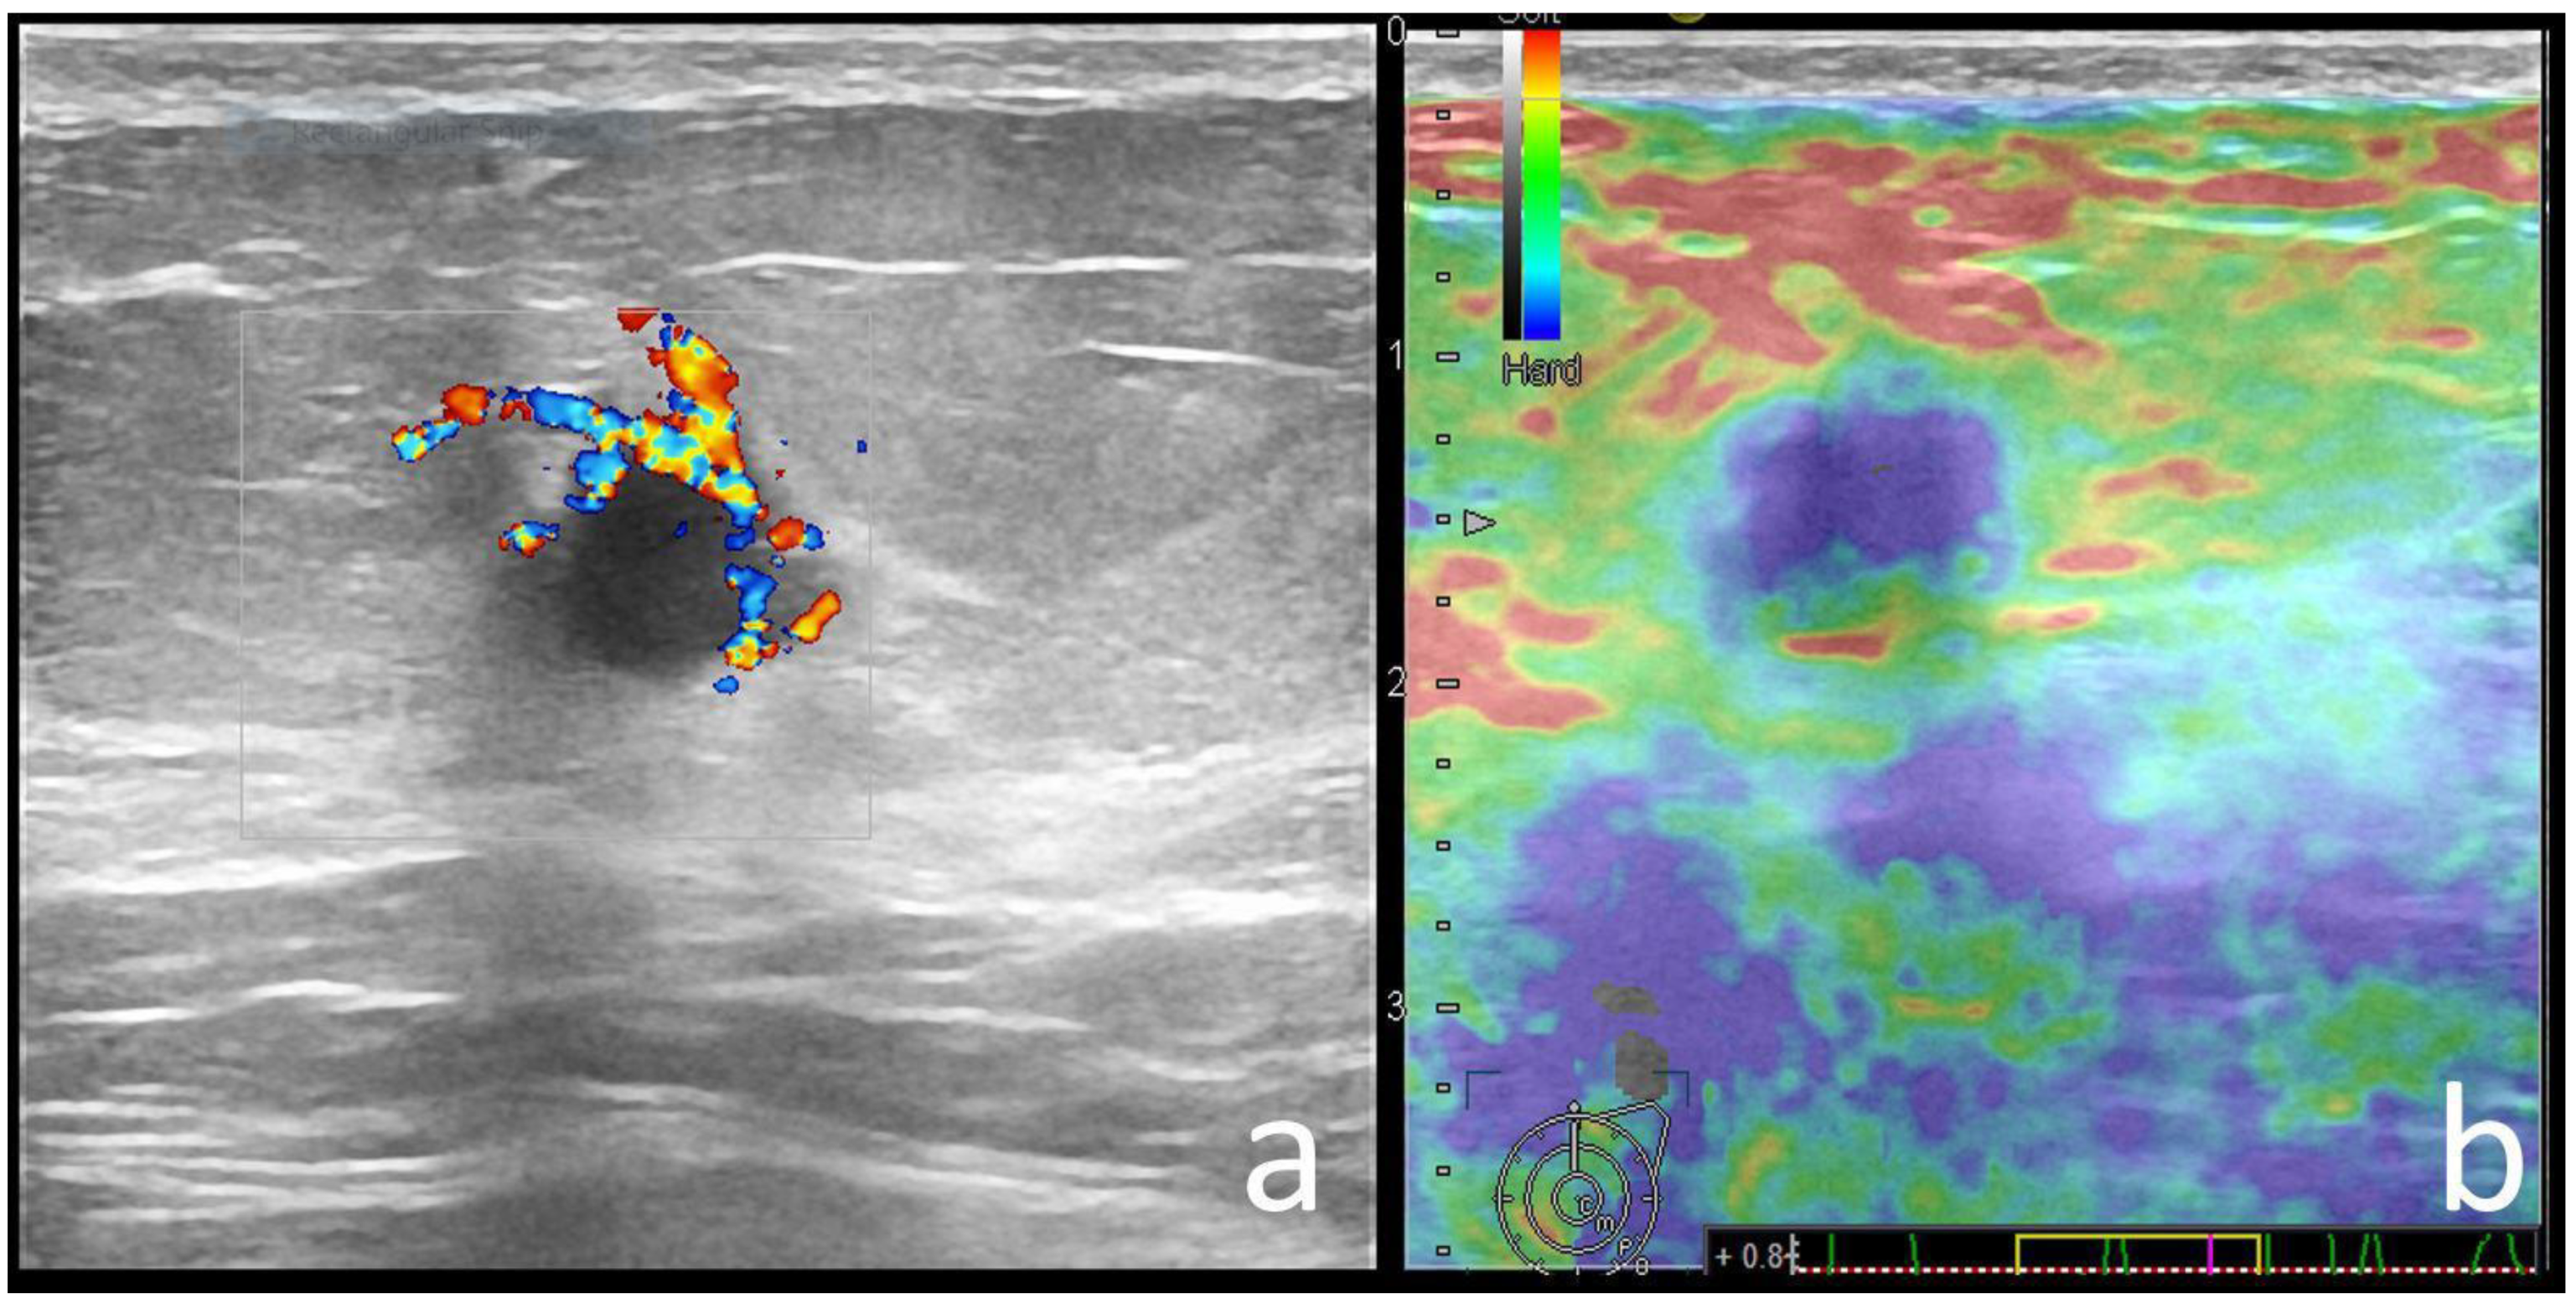

| Color Doppler signal | 0.696 | ||

| Absent | 9 (9.3) | 17 (11.7) | |

| Present | 88 (90.7) | 128 (88.3) | |

| Strain Elastography | 0.029 | ||

| Soft | 40 (40), 9 BGR | 30 (20.6), 1 BGR | |

| Hard | 58 (60) | 115 (79.3) | |

| Echo pattern | Hypoechoic (19/29) | Hypoechoic (9/15) | Heterogeneous (5/15) | Hypoechoic (11/15) | Hypoechoic (4/7) | Heterogenous (3/3) | - | Hypoechoic (2/3) |

| Posterior features | Enhancement (16/29) | Absent (9/15) | Shadowing (6/15) | Enhancement (6/15)/Combined pattern (5/15) | No posterior (4/7) | - | Enhancement (2/3) | - |

| Associated features | Hyperechoic rim (6/29) Soft elastography (11/29) | Calcifications (7/15) Hard elastography (12/15) | Calcifications (7/15) | - | - | Calcifications (3/6) Hyperechoic rim (3/6) | - | Calcifications (2/3) Architectural distortion (2/3) |